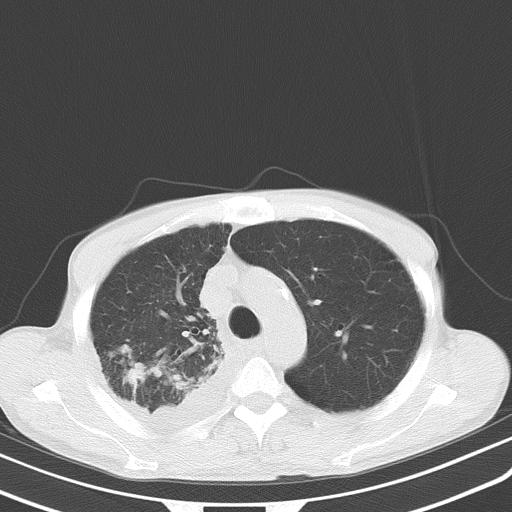

男性 75  咳嗽 一周前发热最高达39

右肺继发型tb并右侧tb性胸腔炎,右侧胸腔大量积液并右下肺膨胀不全,慢支肺气肿、多发肺大泡。建议抽胸水实验室检查并复查排除恶性在占位。

右上肺继发型肺结核,右胸腔中等量积液。

左上肺大泡。

结核的基础上有纵隔淋巴结肿大,右侧有胸水,但右侧纵隔反而窄,说明有肺有不张。

再就是右下肺有块影,和不张混合,还是不能除外肺癌。

1)右肺继发型肺结核。2)左肺胸膜下多发性肺大泡。3)右侧胸腔积液。